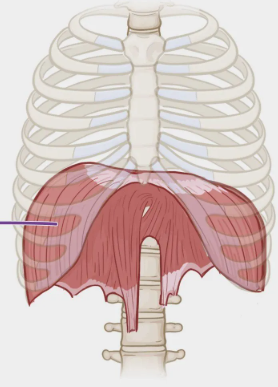

Diaphragm